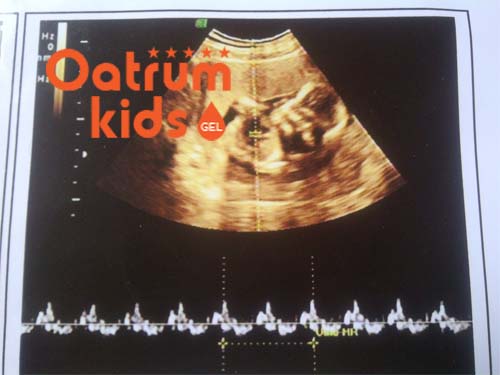

Tim thai là dấu hiệu đặc trưng cho thấy sự sống của thai nhi ở trong bụng. Từ tuần thứ 6 trở đi mẹ có thể biết được âm vang thai của bé và tầm 8 tuần trở đi là có thể đo được nhịp tim của con yêu. Nếu trong khoảng thời gian này thai nhi không có tim thai được cho là dấu hiệu bất thường.

Theo đánh giá của các chuyên gia y tế, tim thai thường sẽ xuất hiện vào tuần thứ 5-6 của thai kỳ nhưng vẫn có một số trường hợp trễ đến tuần thứ 8 hoặc 10. Tuy nhiên việc 6 tuần chưa có tim thai, không nghe được nhịp tim của thai là dấu hiệu đáng lo ngại. Cho nên mẹ cần phải đi kiểm tra định kỳ, nhất là ở giai đoạn tam cá nguyệt thứ nhất.

Dấu hiệu không có tim thai được thể hiện rõ khi siêu âm nhưng không phát hiện thấy âm vang hay nhịp tim thai. Khoảng sau 12 tuần mà vẫn không có tim thai thì chắc chắn là thai đã bị chết lưu. Lúc này giải pháp tốt nhất là nhờ bác sỹ lấy thai ra ngoài gấp để không làm ảnh hưởng xấu đến tính mạng người mẹ.